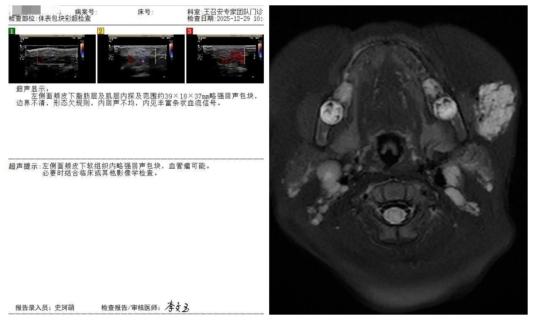

本次治疗的患儿为10月龄男婴,家长于患儿出生1个月后发现其左侧面颊部出现青色包块,初始直径约2cm(硬币大小),随月龄增长逐渐增大至4cm左右(蛋黄大小)。患儿至临沂市人民医院就诊后,经体表包块彩色多普勒超声检查,明确提示“面部血管瘤”,遂以“婴幼儿血管瘤”收住儿内科二病区。

针对该患儿的病情特点与治疗需求,张庆彪主任携手刘海滨副主任医师,带领团队开展多学科术前评估、影像学分析及方案论证,最终确定采用DSA引导下介入硬化治疗方案。手术中,医疗团队依托DSA设备的实时动态成像与“精准导航”功能,经患儿股动脉穿刺建立微创通道,将微导管、导丝精准送达面部血管瘤供血动脉主干,在透视下缓慢注入硬化剂,使病灶血管内皮细胞坏死、管腔闭塞,实现“靶向根治”效果。整个手术过程历时短、创伤仅为穿刺点大小,术后患儿生命体征平稳,病灶即刻呈现萎缩趋势,疗效立竿见影。